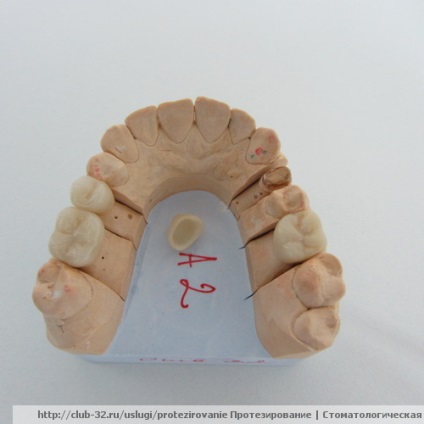

WAX UP A laboratórium diagnosztikai modellek szimulálják jövő formája fogak viasszal (Wax-Up). Szimulációs kiküszöböli a nem precíziós korai szakaszában, hogy kizárják a beteg kényelmetlenséget a jövőben, hogy egészségesek maradjanak, hogy minimálisra csökkentsék az esetleges félreértések között orvosok és a betegek a jövőben fog alakja, valamint más árnyalatok további munkához.

A vágy, hogy mosolyogni, hogy hagyjuk a jó benyomást magáról, egészen természetes. Ugyanakkor egyik feladata egy fogorvos, mint az összes elvárt esztétikai kívánságait a beteg a kezelés előtt pontosabban, hogy megtudja. Azonban a beteg nem mindig tudnak kifejezni a kívánságaikat. Néha csak egy magyarázat szavakban nem elég. A leginkább elfogadható megoldás erre a problémára az, modellezés viasz (Wax-up). Mivel a viasz-up, a végeredmény lehet számítani a lehető legpontosabban! A beteg a végeredményt, és összhangban az érzékek állítsa ego.Uchityvaya említettük, ez a módszer akkor ajánlott, ha bármilyen esztétikai indirekt helyreállítások (koronák, héjak, hidak).